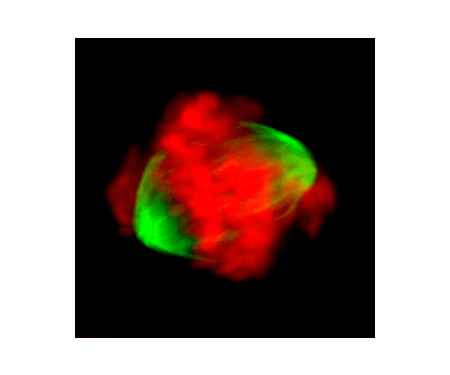

Diagnostic Imaging

Fox Chase Cancer Center is a recognized leader in medical imaging services. We offer a comprehensive range of radiology services using the latest technology to provide our patients with superior service for diagnostic imaging, staging, or determining the extent of the cancer, and cancer treatment planning. Our team of radiology experts offers digital mammography, MRI, CT scan or CAT scan, PET scan, digital X-ray, nuclear medicine and ultrasound.